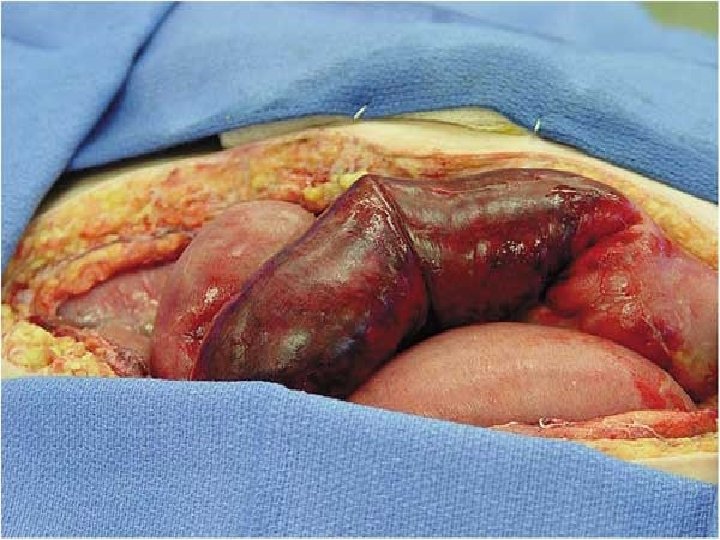

PATHOLOGY 1. The early changes , alteration in capilary permeability. 2. sloughing of epith. Cells at the tip of villi. 3. A membrane of necrotic epith. +fibrin + infla. Cells+bacteria. 4. Edema of sub mucosa with bleeding. 5. Release of endogenous subs. i. e. bact. endotoxin, platelet activating factor. 6. Transmural necrosis

CLINICAL FEATURES Symptoms are nonspecific initially, before evidence of peritonitis presents. Thus, diagnosis and treatment are often delayed until the disease is advanced 1. Medical history may be significant for presence of stroke, MI, or peripheral artery disease 2. Patients may present with a long history of weight loss, postprandial pain, and phagophobia. 3. abdominal pain : severe, acute, unrelenting abdominal pain 4. vomiting 5. frank blood in the stools.

Signs : On abdominal examination , the findings may be minimal. soft abdomen , , no tenderness , , true or sluggish bowel sound , , normal vital signs > if signs of peritonitis present, consider bowel perforation Its difficult to be diagnosed >> because of non- synchronization between the symptoms and the sign